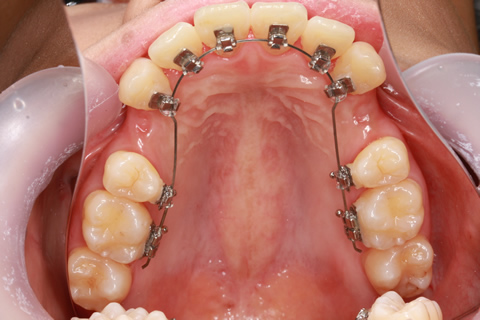

ハーフリンガル矯正3:上の歯のみ舌側矯正で治療(矯正期間24ヶ月)

治療前

治療中(開始直後)

治療中(開始半年後)

治療後

- 年齢・性別

- 25歳女性

- 治療期間

- 2年0ヶ月

- 抜歯

- 上下4番抜歯

- 治療費

- 110万円

- 治療内容

- 施術の副作用(リスク)

- 表側矯正と比較して、力学的な操作性が複雑なため、ボーイングエフェクトを起こしやすい。